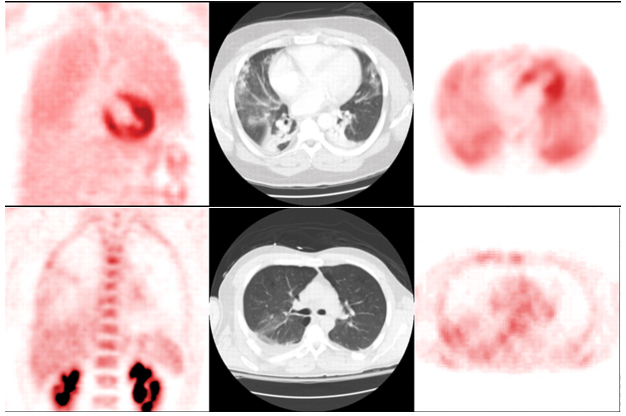

肺通气的超声征象分为四组:①正常模式(N),表现为肺滑动征伴A线或孤立的B线(<3),记0分;②肺通气中度丧失,出现多条B线(>3),记1分;③严重的肺通气损失,显示为融合B线,记2分;④肺组织实变征象记3分。在分析过程中,每一个特定的区域最差的超声波征象为计分标准,并将所有点的得分相加。结果显示,肺部超声评分(LUS)与多个ARDS预后指标[血管外肺水指数(EVLWI),肺损伤评分(lung injury score,LIS),呼吸系统顺应性(Crs),氧合指数]密切相关,能够准确评估ARDS治疗的疗效,如PEEP的设定、肺复张的疗效,并能够预测ARDS患者死亡风险。与其他检查相比,肺部超声是一种无创、经济、可重复、简单的床旁检查方法,但肺气肿、肥胖、导管敷料等都影响超声的评定,测量参数有一定的主观性。弥漫性肺泡损伤(DAD)是ARDS的病理标志。一项研究分析了是否可以使用高分辨率CT(HRCT)评分来预测与DAD相关的60 d死亡率,研究共纳入34例在ARDS诊断后7 d内接受HRCT的DAD患者,并被分为60 d存活组和未存活组,每组17例患者。采用Ichikado等提出的HRCT评估急性间质性肺炎评分系统评估ARDS,HRCT表现根据分级系统按1~6分进行评分,1分为正常衰减,2分为磨玻璃影,3分为实变,4分为磨玻璃影伴牵引性支气管扩张或细支气管扩张,5分为实变伴牵引性支气管扩张或细支气管扩张,6分为蜂窝状。单因素和多因素二元回归分析以及ROC曲线显示,牵引性支气管扩张或细支气管扩张的总面积百分比是60 d死亡率的独立预测因子,具有良好的预测性能。存活患者的HRCT表现为广泛的磨玻璃影和实变,支气管壁光滑(图4B)。未存活患者的HRCT表现为双侧磨玻璃影、网状和明显的牵引性支气管扩张(图4D红色箭头)。图源:J Clin Med, 2022, 11(9):2458.肺部炎症是ARDS的关键特征之一。氟代脱氧葡萄糖(FDG)是一种具有生化活性的葡萄糖抗代谢产物,FDG被组织细胞吸收后可在PET-CT扫描显像。中性粒细胞活化在代谢上的特征是每个细胞的葡萄糖利用率增加,从而增加FDG摄取。在急性肺损伤(ALI)期间,FDG PET可用于监测肺中性粒细胞活化情况。同时,在ALI状态下,巨噬细胞对FDG信号的变化较小,淋巴细胞在体外激活后FDG摄取增加。内皮细胞活化后具有高度代谢活性,摄取FDG增强,肺泡上皮细胞受损后也可以促进FDG的摄取。因此,FDG PET可能是一种有价值的非侵入性方法,可用于全面了解ALI/ARDS的发病机制,早期预测ARDS的发生和评估预后。研究发现,单侧吸入烟雾导致急性损伤的单侧绵羊肺中区域FDG摄取显著增加(图5,图6)。在该模型中,区域FDG标记葡萄糖摄取可以预测区域气体交换损伤,表明存在功能-炎症关系。研究结果还表明,损伤前的通气-灌注异质性程度与损伤后FDG摄取的程度之间存在直接关联。

图源:AJR Am J Roentgenol, 2010, 195(2):292-300.图6  单纯吸入烟雾以及吸入烟雾和呼吸机肺损伤双重打击的绵羊肺图源:AJR Am J Roentgenol, 2010, 195(2):292-300.Musch等发现在机械通气后90 min,在呼吸机诱发的肺损伤绵羊模型中可以检测到仅由机械力引起的区域FDG摄取增加(图7)。图7  三只羊暴露于单侧呼吸机引起的肺损伤,早期出现FDG浓聚图源:AJR Am J Roentgenol, 2010, 195(2):292-300.Rodrigues等针对FDG PET的预测价值对8例肺挫伤患者进行了研究,其中没有一例患者最初符合ARDS的标准。入院后24~72 h,在FDG PET中,后来发生ARDS的4例患者中有3例在整个肺部有弥漫性FDG摄取,但后来未发生ARDS的4例患者仅在CT图像上局灶性肺混浊区域有显著的FDG摄取(图8)。后来发生ARDS的患者正常通气肺的FDG摄取值高于未发生ARDS的患者,这表明FDG PET在ALI早期阶段提供了很有价值的预测信息。图8  因胸部创伤和肺挫伤入院的患者,高浓聚者后来发生ARDS图源:AJR Am J Roentgenol, 2010, 195(2):292-300.6. 运用生物信息学和转录组学技术筛选ARDS预后标志物在ARDS肺泡巨噬细胞中发现的转录组学生物标志物可以预测机械通气的危重症患者预后。研究收集了35例受试者的68个BALF样本,这些样本均在ARDS发生48 h内采集,从24526个基因中筛选4个分子——ADORA3,GNB1,NTS,RHO。其中ADORA3(adenosine A3 receptor)主要是调控炎症因子和免疫反应。研究表明,ADORA3及其相关通路变化与28 d死亡率明显相关,ADORA3有可能成为评估ARDS预后的关键基因。有研究纳入2016年1月至2019年6月期间的196例脓毒症患者和入组时196名健康个体的血浆样本。结果发现,与健康人相比,ARDS脓毒症患者和非ARDS脓毒症患者的miRNA-103和miRNA-107均降低,ARDS脓毒症患者的miRNA-103和miRNA-107均低于非ARDS脓毒症患者。miRNA-103和miRNA-107降低预示着脓毒症患者ARDS和28 d死亡风险增加。miRNA-103和miRNA-107是脓毒症ARDS患者28 d死亡率的预测标志物。另外一项研究纳入脓毒症患者150例和健康受试者150例(健康对照)。与健康对照组相比,ARDS脓毒症患者和非ARDS脓毒症患者miRNA-125a和miRNA-125b相对表达增加,而与非ARDS脓毒症患者相比,ARDS脓毒症患者仅miRNA-125b升高,而miRNA-125a没有升高。miRNA-125b在预测ARDS风险方面有较高的价值。